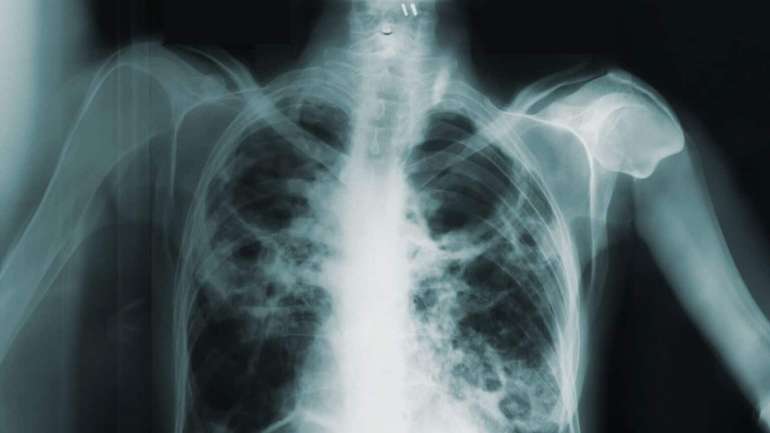

Кашель не головний симптом туберкульозу — науковці

Про результати свого дослідження науковці розповіли у статті для міжнародного медичного журналу The Lancet Infectious Diseases. Зазначається, що інфекційне захворювання провокується різними видами мікроорганізмів із групи Mycobacterium tuberculosis complex.

Згідно із комплексним експериментом, проведеного у Замбії, Лаосі, Ґамбії, Камбоджі та Південній Африці, 60% пацієнтів із туберкульозом не повідомляли про постійний кашель. У третини з них протягом понад місяць спостерігалися інші симптоми, що вказують на сухоти й тільки у 9% зовсім не було ознак хвороби.

Науковці наголошують, що туберкульоз без симптомів найчастіше зустрічається у молодших людей, жінок та мешканців міст (здебільшого перенаселених нетрів — прим. ред.). Водночас сухоти із меншою ймовірністю дає позитивні результати мазків: їхню частку оцінили у 29,1%.

«Більшість людей, хворих на туберкульоз, не повідомляють про кашель. Чверть наших піддослідних узагалі не відзначають симптомів, які б вказували на це захворювання. Тобто підтвердити наявність хвороби ми змогли лише після відвідин того чи іншого пацієнта.

Проте чверть із тих, хто не має кашлю, мають позитивні мазки мокротиння, що вказує на їхнє зараження і заразність. В умовах високої захворюваності субклінічний туберкульоз може ставати справжнім тягарем цієї хвороби та підвищувати ризики передачі мікобактерій оточенню», — підсумували автори дослідження.